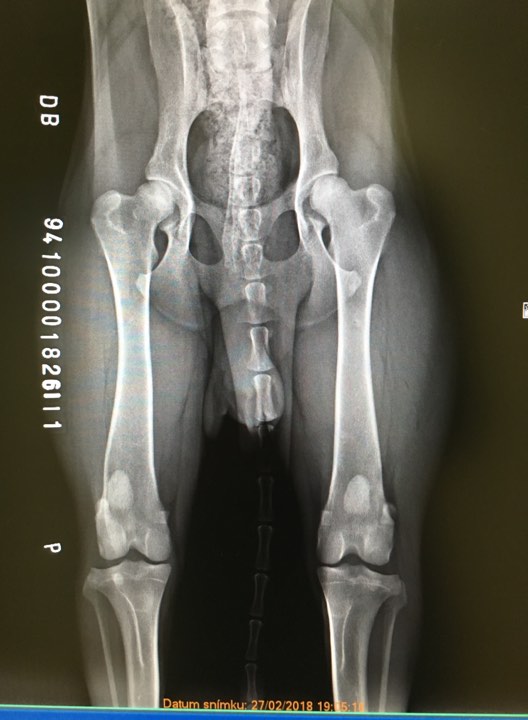

X-ray of HD is HERE, X-ray of ED is HERE